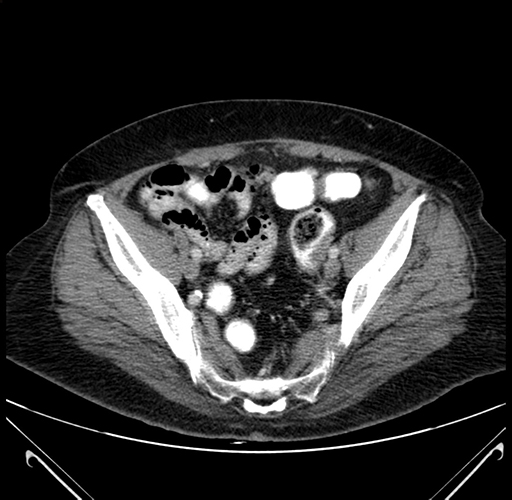

Pre-Chemo: Axial Venous

Axial Venous